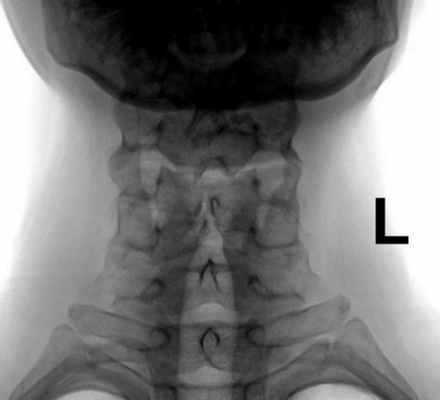

На рентгенограмме в прямой проекции определяется центрально расположенная полоса просветления в пределах контуров задней дуги атланта. На спондилограмме в боковой проекции отмечается отсутствие внутреннего контура основания остистого отростка (рис.1, В).А В.

Рис.1. Аномалия развития. Врожденное незаращение задней дуги атланта. Spina bifida posterior C1. Рентгенограммы и схемы шейного отдела позвоночника в прямой (А) и боковой (В) проекциях. Условные обозначения, здесь и далее: поз. «а» - рентгенограмма, «b» - схема. На рентгенограмме в прямой проекции определяется расщелина задней дуги атланта. На рентгенограмме в боковой проекции отсутствует внутренний контур позвоночного канала в основании остистого отростка С1.

Рис. 5. Аномалия развития. Полный блок (слияние тел и дуг С2-С3). На рентгенограммах и схемах шейного отдела позвоночника в прямой (А) и боковой (В) проекциях отмечается отсутствие межпозвонкового диска С2-С3, остистые и суставные отростки соединены.